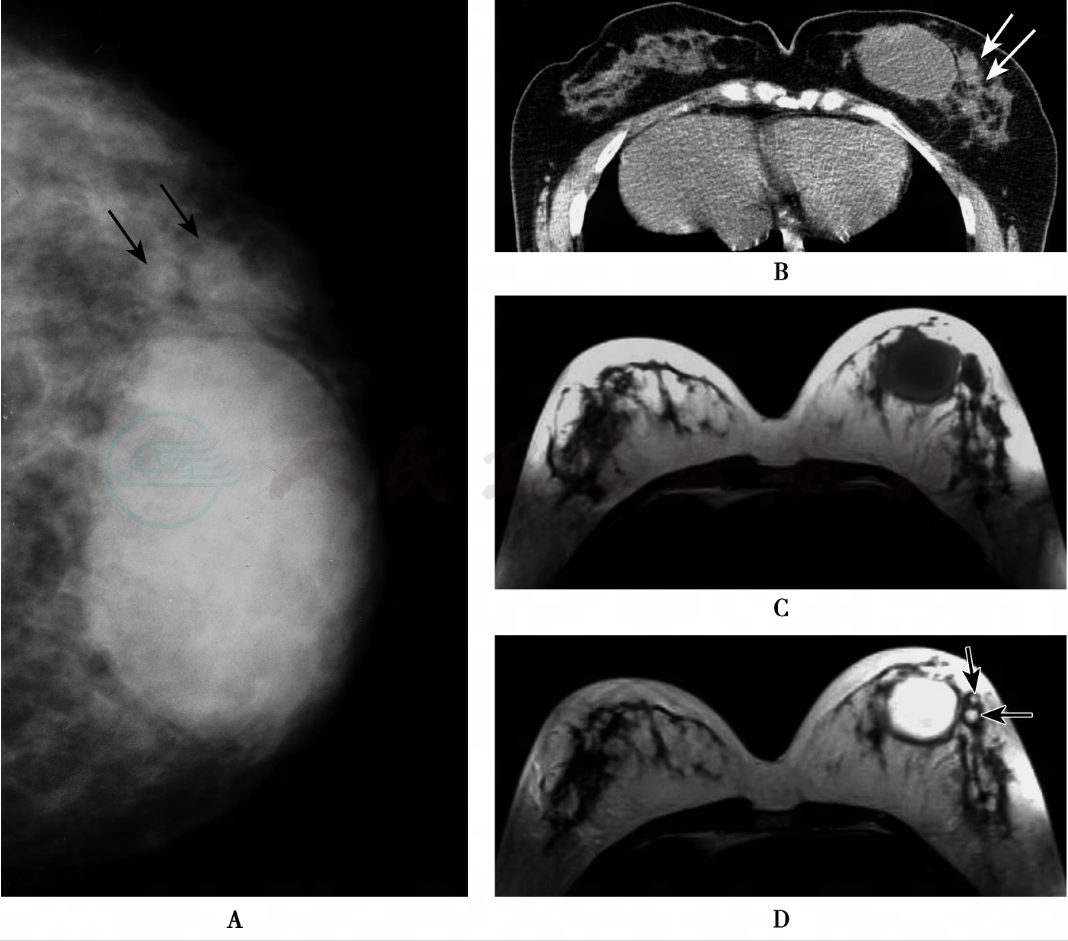

图3 乳腺脓肿MRI成像

注:37岁,女性。A.左乳X线头尾位片,显示左乳内上高密度肿物,肿物大部分边缘清晰、规则,部分后缘显示模糊,其内未见钙化,该肿物外侧尚可见两个小结节(黑箭),密度与腺体密度相近,边缘尚光滑;B.CT平扫,显示左乳内侧肿物,边界清楚,其内部CT值为11.4HU,肿物壁密度稍高且较厚,其外侧亦可见两个小结节(白箭),边界清楚;C.MRI横轴面平扫T1WI;D.MRI横轴面平扫T2WI,左乳内侧见一个类圆形肿物,肿物于T1WI呈低信号,T2WI呈高信号,表现为液体信号特征,边界清楚,肿物周边的壁厚度大致均匀,内壁光滑整齐。该肿物外侧亦可见两个信号与之相同的小结节(黑箭),边界清楚。